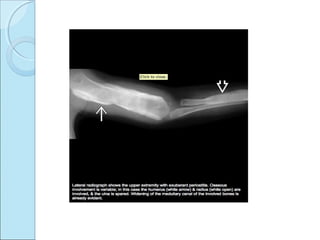

RADIOGRAPHIC FEATURESRADIOGRAPHIC FEATURES

 Marked periosteal proliferation.

 Cortical thickening.

 Soft tissue swelling.

Osteoblastic periosteal lesion involving shaft of ulna

,also lateral aspect of radius.

Deformity, periosteal reaction. Soft tissue

swelling.